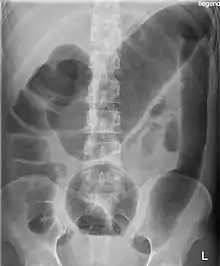

Massively dilated colon with air-fluid level can be seen on abdominal radiograph or CT scan.[5][6]